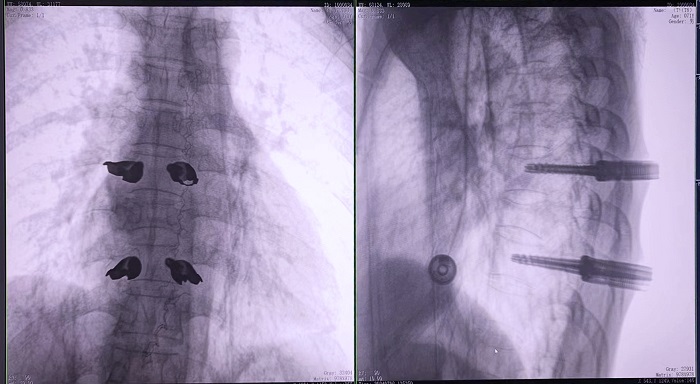

③機(jī)器人輔助胸椎手術(shù)操作難點(diǎn)之精準(zhǔn)置釘

傳統(tǒng)開放手術(shù)中,胸椎的手術(shù)視野相對受限,螺釘?shù)闹萌胫饕蕾囉卺t(yī)生的經(jīng)驗(yàn)和手感,存在一定的主觀性。

普愛醫(yī)療手術(shù)導(dǎo)航定位系統(tǒng)解決方案

普愛醫(yī)療骨科手術(shù)機(jī)器人的高精度機(jī)械臂,按照規(guī)劃好的路徑及角度,自動精準(zhǔn)定位穿刺點(diǎn),醫(yī)生打入克氏針后,正側(cè)位圖像顯示精度滿足預(yù)期,醫(yī)生完成置釘?shù)群罄m(xù)手術(shù)操作。